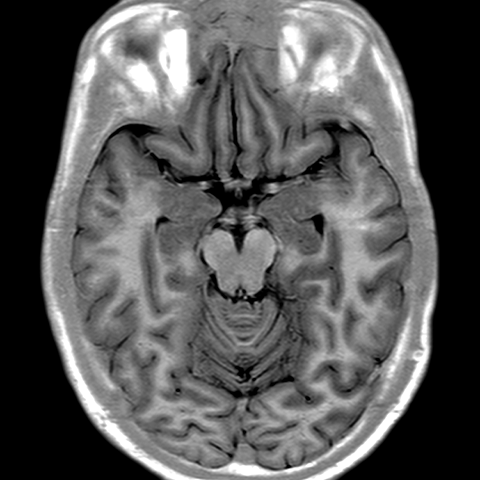

Cerebral Hemispheres, MR (normal) [5 of 9]